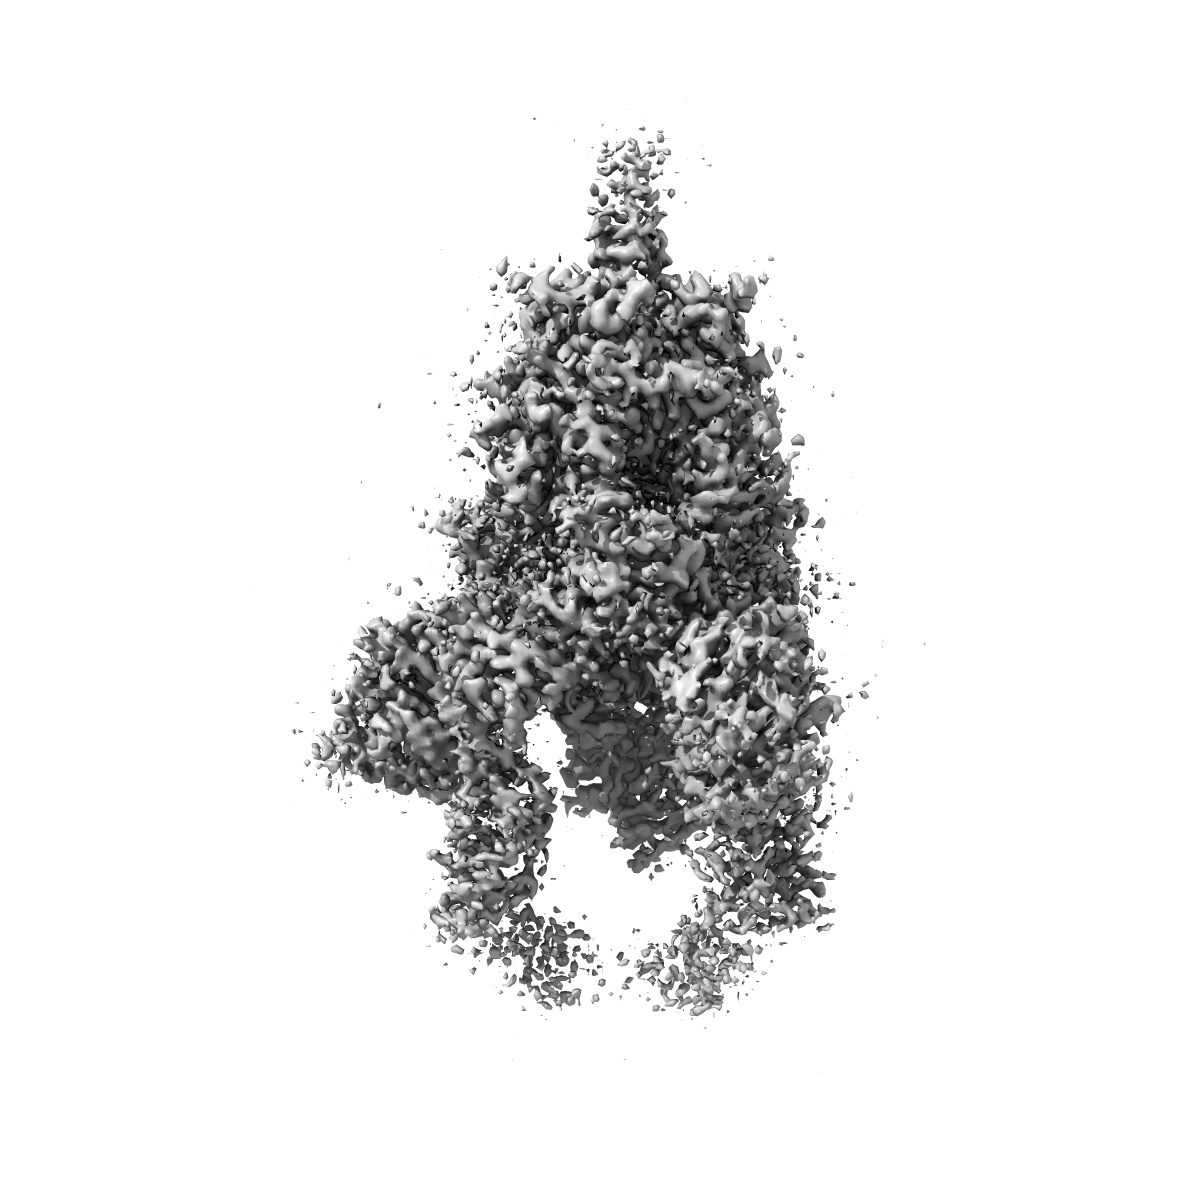

Structure of the SARS-CoV-2 spike glycoprotein in complex with the 10D12 heavy-chain-only antibody (2 RBDs up)

Single-particle3.3 Å

Sample: SARS-CoV-2 spike glycoprotein in complex with the 10D12 heavy-chain-only antibody